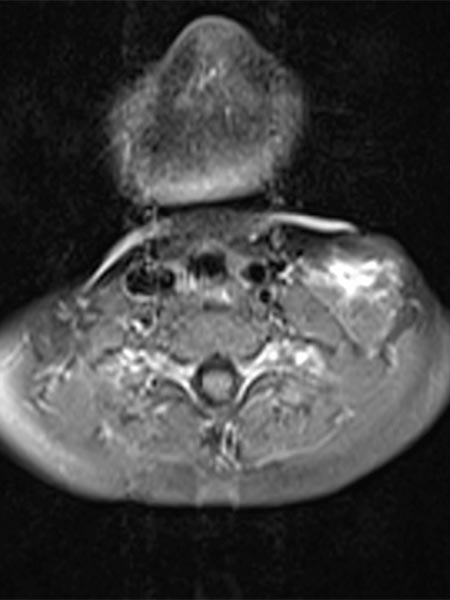

In der axialen MRT (T2-Wichtung) zeigt sich ebenfalls die dorsale Lage des größeren hypointensen Thrombus innerhalb der stark hyperintensen venösen Malformation. Zudem ein klassischer Flüssigkeits-Flüssigkeits-Spiegel innerhalb der VM. Die etwas signalärmeren, korpuskulären Bestandteile setzen sich mit der Schwerkraft nach dorsal ab (Rückenlage), das etwas signalreichere Blutserum „schwimmt“ oben (ventral) auf, dazwischen bildet sich ein Spiegel.

Die axiale MRT (T1-Wichtung) auf gleicher Höhe nach Kontrastmittelgabe zeigt eine zentrale Anreicherung innerhalb der venösen Malformation. Diese Anreicherung ist jedoch relativ langsam und erst Minuten nach KM-Injektion feststellbar und zum Zeitpunkt der Aufnahme noch unvollständig.